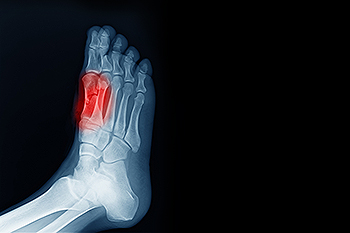

Sesamoiditis causes pain beneath the big toe and is often exacerbated by weight-bearing and specific footwear choices. The two tiny sesamoid bones, located just below the big toe, are integral to foot locomotion. They can be affected by direct trauma or positional changes, especially in individuals with high-arched feet, bunions, or those who wear high heels. For dancers, joggers, and those individuals with certain foot structures, the discomfort associated with sesamoiditis can be particularly challenging. Diagnosis by a podiatrist relies on examination of the toe, and determining range of motion. Other tests, such as synovial fluid analysis and X-rays, may be used to exclude infection and fractures. Pain from sesamoiditis is often intensified by walking and may involve inflammation, warmth, and swelling around the 1st metatarsophalangeal, or MTP, joint. Footwear modification and custom orthotics can play a pivotal role in managing symptoms. Wearing thick-soled shoes may also help alleviate sesamoid pressure. In cases where a sesamoid fracture without displacement is identified, treatment involves immobilizing the joint with a flat, rigid, surgical shoe. For help with pain resulting from sesamoiditis, it is suggested that you schedule an appointment with a podiatrist for an exam and treatment.